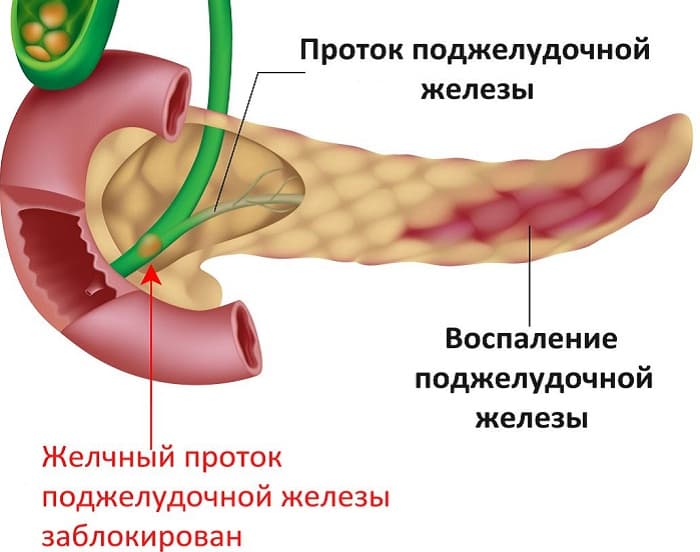

Как лечить – скажет врач. Самолечение здесь может только навредить. Боли в поджелудочной железе говорят о том, что в ней началось воспаление. Такое заболевание называется панкреатит. Для его начала должны быть весомые причины, чтобы в поджелудочной образовалось воспаление.

Причины воспаления ПЖ

Поджелудочная железа участвует в переваривании пищи с высоким содержанием жиров, белков, углеводов. Одна из ее функций – регулирование обмена углеводов, при котором образуются и проникают в кровь глюкагон и инсулин. Насчитывается множество факторов, негативно влияющих на состояние органа.

Причинами заболевания ПЖ являются:

- употребление алкогольных напитков;

- как вторичное заболевание при образовании конкрементов в органе и его протоках;